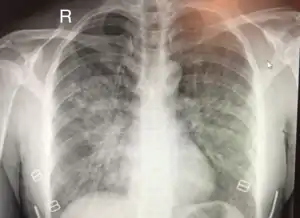

Chest x-ray of HAPE showing characteristic patchy alveolar infiltrates with right middle lobe predominance.

Hypoxic pulmonary vasoconstriction (HPV) occurs diffusely, leading to arterial vasoconstriction in all areas of the lung. This is evidenced by the appearance of "diffuse," "fluffy," and "patchy" infiltrates described on imaging studies of climbers with known HAPE.[8]

On physical exam, increased breathing rates, increased heart rates, and a low-grade fever 38.5o (101.3o F) are common.[8][3] Listening to the lungs may reveal crackles in one or both lungs, often starting in the right middle lobe.[8][3] Imaging studies such as X-ray and CT imaging of the chest may reveal thoracic infiltrates that can be seen as opaque patches.[13][8][3] One distinct feature of HAPE is that pulse oximetry saturation levels (SpO2) are often decreased from what would be expected for the altitude. People typically do not appear as ill as SpO2 and chest X-ray films would suggest.[8][3] Giving extra oxygen rapidly improves symptoms and SpO2 values; in the setting of infiltrative changes on chest X-ray, this is nearly pathognomonic for HAPE.[3]